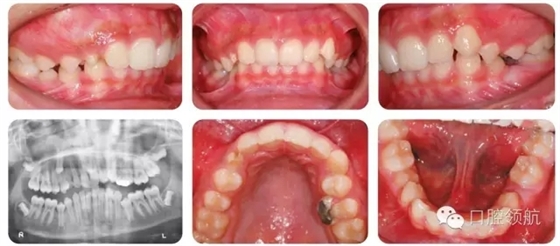

13歲的男性患者的錯牙合畸形如圖2.42所示。

全景片情況

● 全景片確認了該患者4顆第三磨牙均存在。

● UR3未萌出,牙冠略向遠中傾斜,并接近UR4的牙根。

● UR3根尖孔未閉合。

● 下頜雙側第二前磨牙垂直阻生。

● 未萌牙的發(fā)育無病理因素存在。

● 13歲男性患者,I類關系,輕度骨性II類,均面型。

● 雙側磨牙I類關系,中線齊,雙側尖牙1/2牙尖II類關系。

● 另外伴有:

○ 1. 異位UR3。

○ 下頜第二前磨牙阻生。

○ 深覆牙合。

○ 上下牙列均存在擁擠。